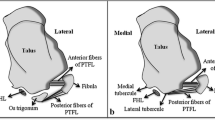

We found connections between the os trigonum and PTFL, PTCL, OF-FHL, paratenon and FTCL, and FR both in the experimental and control group (Table 1). The connections have the form of narrow, partly communicating fiber bands in both groups. The ligament most commonly connected to the os trigonum was the PTFL (Table 1 and Fig. 1). In most cases of the experimental group, the posterior part of the PTFL inserted on the os trigonum (n = 89, 85.6%), while in 10 (9.6%) cases, the whole PTFL inserted on the os trigonum (Fig. 1). In five (4.8%) cases of the experimental group, the PTFL inserted only on the posterior process of the talus, and no attachment to the os trigonum was noticed (Fig. 1). In all cases in the control group, the PTFL inserted on the posterior process of the talus (Table 1).

Three variants of the insertion of the PTFL. PD-weighted—a–c 1a—anterior part of the PTFL inserts on the talus; 1b—posterior part of the PTFL inserts on the os trigonum; 2—the PTFL inserts only on the os trigonum; 3—the PTFL inserts only on the talus; 4—the FTCL; 4a—the inferolateral lamina of the FTCL; 5—the FHL runs directly on the articulation of the os trigonum

The PTCL was identified in 98 (94.2%) cases of the experimental group, of which in 54 (51.9%) cases inserted on the os trigonum, while in 44 (42.3%) cases, it inserted on the posterior process of the talus (Fig. 2). No clear PTCL was noticed only in 6 (5.8%) cases of the experimental group. In the control group, the PTCL was noticed in 94 (90.4%) cases (p < 0.001), while no clear ligament was seen in the remaining 10 (9.6%) cases. An accessory projection from the PTCL to the posterior outline of the joint capsule was noticed in 37 (35.6%) cases of the experimental group. Posterior to the os trigonum, a "fibrotic node-like structure" (Fig. 3) was visible in 41 (39.4%) cases vs. 43 (41.3%) cases in the control group (p > 0.05). The surrounding structures received fibrotic projections from fibrotic node-like structure (Figs. 2 and 3).

Connections to the PTCL. PD sequences for the same patient—a–d. The direct connection between the os trigonum and calcaneus via the PTCL, which branches in the fascicle to the calcaneus (1) and to the medial tubercle on the posterior process of the talus (2). The connections via the node-like structure (3) to the calcaneus (2) and to the superior peroneal retinaculum by means of the FTCL (4)

The connection to the OF-FHL (Fig. 4) was seen directly in 44 (42.3%) cases or through the fibrotic node (Fig. 3) mentioned above in 23 (22.1%) cases of the experimental group. FHL runs in most cases at the level of articulation between the os trigonum (n = 66, 63.5%), followed by the posterior process of the talus (n = 26, 25%) (Fig. 1) and less often on the os trigonum (n = 12, 11.5%) (Fig. 5).

Connections to the FTCL. PD sequences for four different patients (a–d). The os trigonum (1) connects with the superior peroneal retinaculum by a band (2) from the fibulotalocalcaneal ligament (3). The connection between the os trigonum and osteofibrous tunnel of the flexor hallucis longus can be seen (4)

The FTCL is a delicate thin fibrous lamina set in the frontal plane located between the os trigonum (n = 93, 89.4%) or the posterior process of the talus in the experimental group (n = 95, 91.3%), p > 0.05), medial and lateral malleolus and paratenon posteriorly. At the insertion on the lateral malleolus, the FTCL connected to the calcaneofibular ligament in 4 (3.8%) cases in the experimental group and in 9 (8.7%) cases in the control group (p < 0.05). The connection between the os trigonum and superior peroneal retinaculum via the FTCL was seen in 31 (29.8%) cases of the experimental group (Fig. 5). The FTCL prolonged medially into the FR in 89 (85.6%) cases in the experimental group and 91 (87.5%) cases in the control group (p > 0.05). The os trigonum was connected to the paratenon via the FTCL more often from the lateral side (n = 33, 31.7%) compared to that in the medial side (n = 6, 5.8%). The corresponding values in the control group were generally higher (n = 67, 63.8%, p < 0.001) for the lateral side compared to those in the medial side of the paratenon (n = 31, 29.5%, p < 0.01). The medial expansion of the FTCL connected with the plantaris tendon in n = 57 (54.8%) in experimental group in while in control group (n = 52, 50%, p > 0.05). The plantaris tendon was connected directly to the paratenon in (n = 19, 18.2%) cases in the experimental group and in (n = 23, 22.1%) cases in the control group (p > 0.05). The absence of a connection of the plantaris tendon with ligament projections included in the study was noticed in (n = 28, 26.9%) in the experimental group and (n = 29, 27.9%, p > 0.05) in the control group.

a Prominent connections of the os trigonum, PD sequence. b General map of the communications between different fibrotic structures at the level of the os trigonum. 1—PTFL, 2—connection to the osteo-fibrosus tunnel of the FHL, 3—FTCL, 3a—branch of FTCL to the os trigonum, 4—connection to the Kager’s fat pad